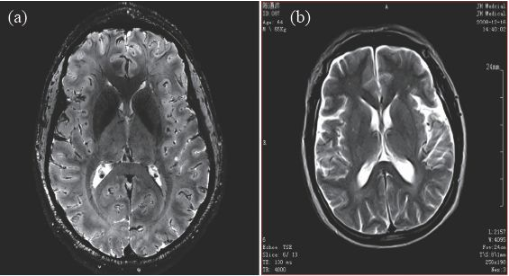

因此,磁共振成像技术目前的发展趋势,是朝着更高磁场强度发展,以期获得更高分辨率的图像,并实现多核成像。图6 显示了磁场强度的高低对图像分辨率的影像,(a)为7 T 磁场下的图像,(b)为0.35 T磁场下的图像,二者的图像分辨率可见一斑。

图6 T2 加权成像(a)7 T 下的成像,分辨率约0.3 mm;(b)0.35 T下的成像,分辨率约1 mm